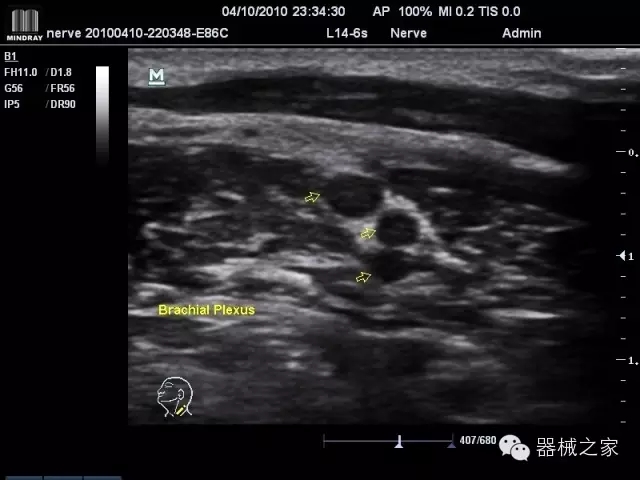

經(jīng)典產(chǎn)品:M7(星鉆)

臨床圖片賞析